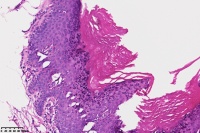

脂溢性角化症伴皮角?

女

年龄

49岁

手臂皮肤组织

图2

脂溢性角化病